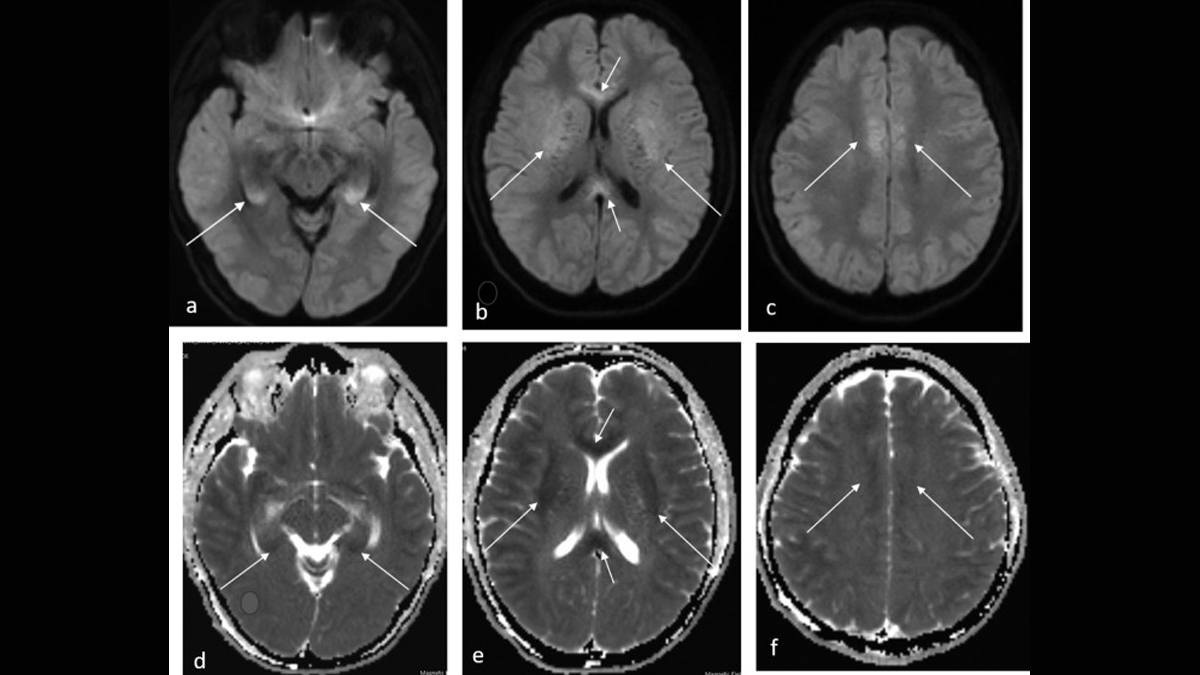

Malaria usually starts with a mosquito bite. The parasite gets into your blood and infects your red blood cells. In cerebral malaria, these infected cells get stuck in the tiny blood vessels in your brain. This blocks blood and oxygen from reaching brain cells.

Dr Inamdar says, “When the parasite blocks the blood vessels in the brain, the brain does not get enough oxygen. This can make the brain swell and stop working properly. Even after treatment, some people may have trouble with memory, speech, or movement.”